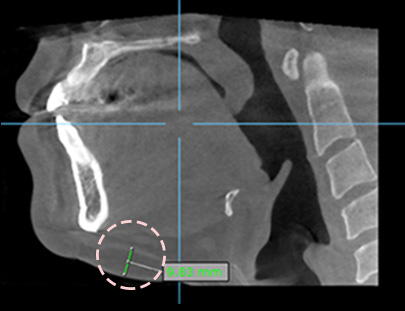

3D-CT拍摄后

进行面诊

准确的分析

脂肪分布

爱她3D-CT 面部吸脂是拒绝用触感来判断的手术。 通过3D-CT拍摄后 确认是否需要抽取肌肉内侧脂肪 精致雕塑! 通过细小针管,几乎没有痛症,淤青,浮肿!通过强效超声波吸脂后维持弹力!无需手术即可快速恢复的,简单解决面部小的苦恼。韩国面吸,韩国面部脂肪吸脂,面吸,面部吸脂,瘦脸,小V脸,韩国爱她整形外科,韩国爱她整形,韩国atop整形外科,韩国atop 愛她3D-CT 麵部吸脂是拒絶用觸感來判斷的手術。 通過3D-CT拍攝後 確認是否需要抽取肌肉內側脂肪 精緻雕塑! 通過細小針管,幾乎沒有痛症,淤青,浮腫!通過強效超聲波吸脂後維持彈力!無需手術即可快速恢複的,簡單解決麵部小的苦惱。韓國麵吸,韓國麵部脂肪吸脂,麵吸,麵部吸脂,瘦臉,小V臉,韓國愛她整形外科,韓國愛她整形,韓國atop整形外科,韓國atop